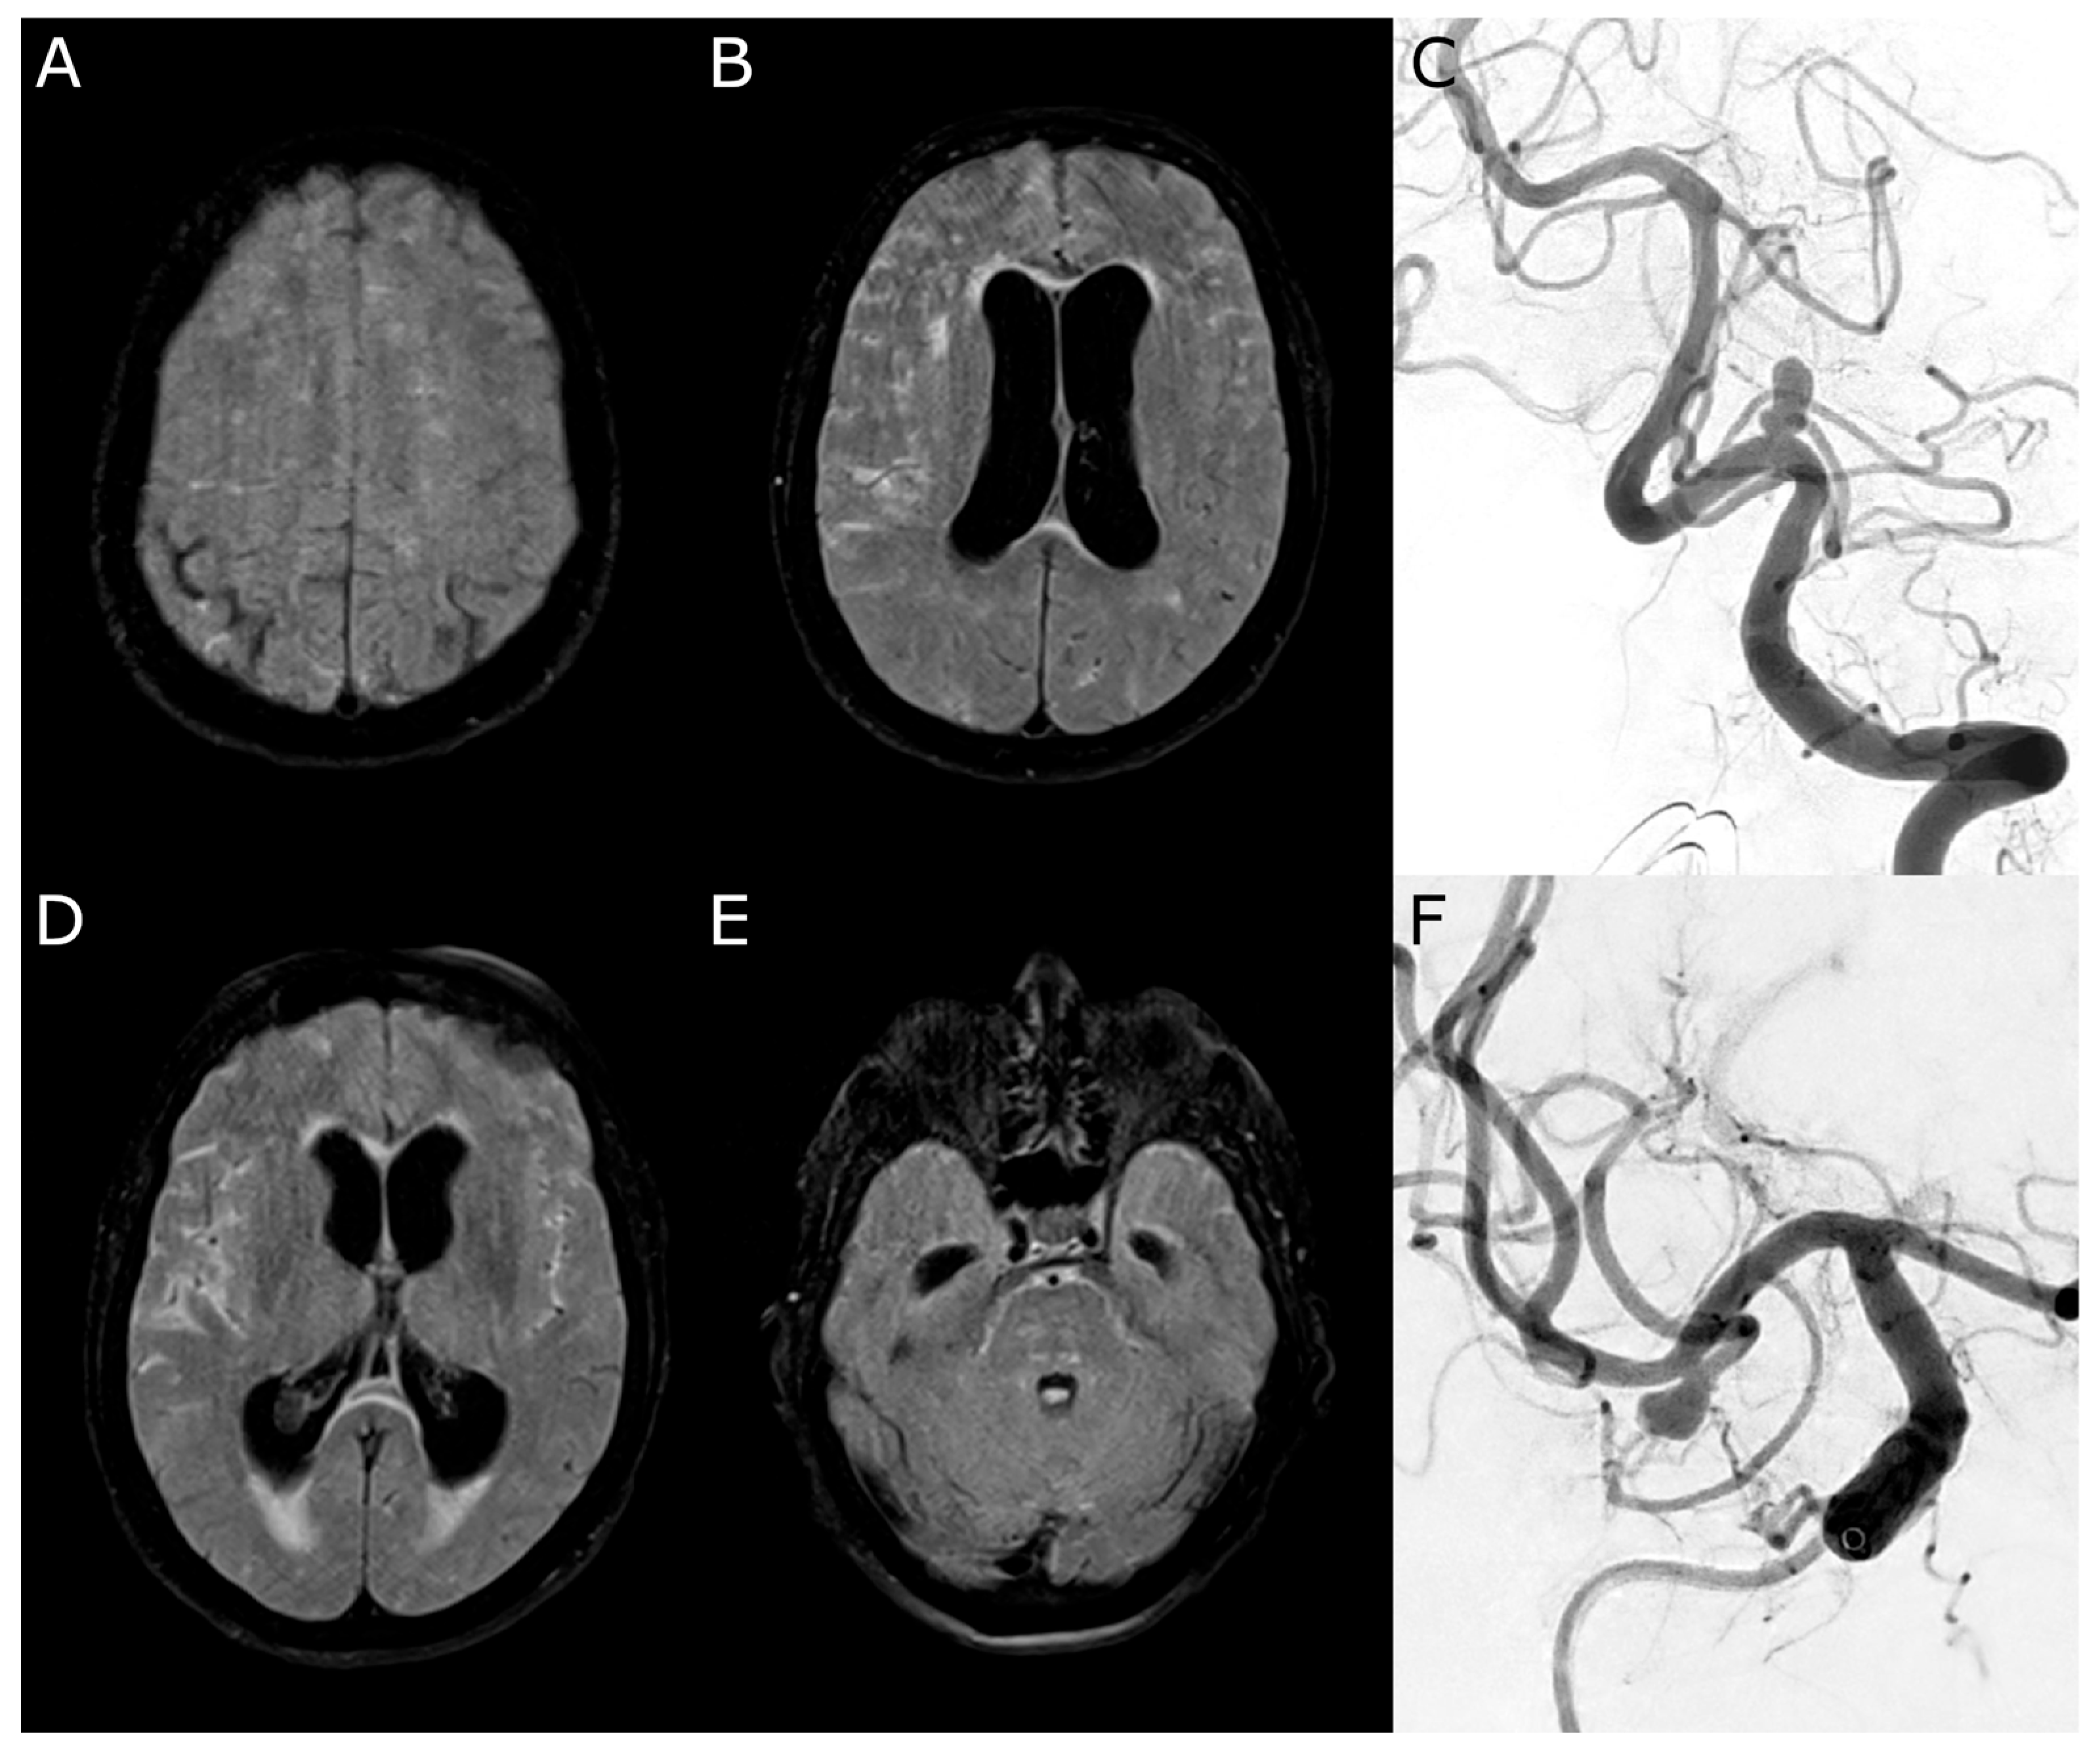

3.10. Case 1

3.11. Case 2